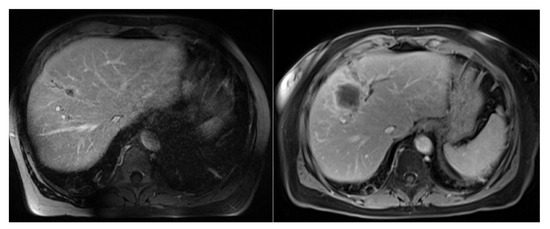

2.2. Radiotherapy Planning and Delivery